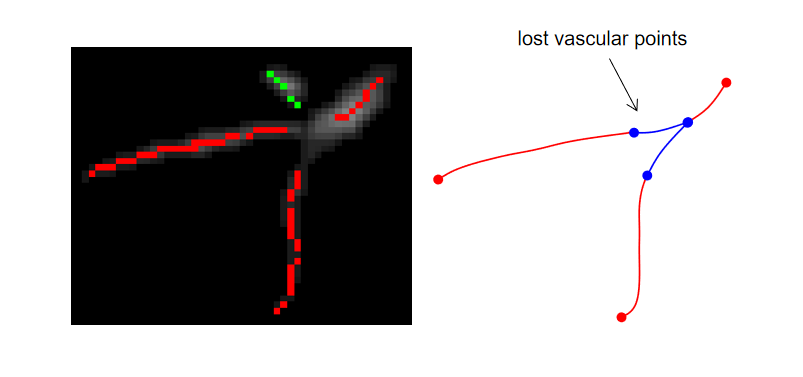

Firstly, based on the characteristics of vascular tubular structure, the scale-space particle reconstruction algorithm was used to extract the initial skeleton of the vessel and obtain the local information of the vessel mask. Scale-space particles sampling method exploits the theory of linear scale-space to localize the features of the image described by the Hessian. The vascular tree is represented as a set of particles that each contains vessel scale, orientation, and intensity information. Therefore, particles are represented as X = {}, where represents a particle point. However, after vascular tree reconstruction, the vessels are discontinuous, which is due to the inability of this method to identify non-tubular structures, such as the junction of vessels, resulting in partial point loss. At the same time, there was no parent-child relationship between the particles.

Secondly, the skeleton extraction algorithm based on distance transform can maintain the connectivity of the vascular tree. MSFM is used to obtain the global information from the vessel mask, and the vessel point path is obtained by iteratively tracing from the end of the potential tree to the root node, where the branch online confidence score is calculated in the time map to determine whether the trace iteration should be updated or excluded from the skeleton tree. In this paper, 3D vessel mask is taken as the input with 3D coordinates x, aiming to output the vessel skeleton tree G, and a 3D spatial coordinate and radius are specified for each vessel skeleton tree G node. The degree of each vascular tree node can be between 1 and 3. However, the radius of each node of the obtained vessel tree is only an approximation and does not really reflect the vascular tubular shape, and the results after reconstruction are different from the real vascular tree to some extent.

Finally, in order to ensure the continuity and authenticity of the topology reconstruction, we flexibly combined the global and local information of the vascular skeleton. In this paper, a particle-based 26-neighborhood search method is used to extract the topological structure of the final vessels by guiding the time map to make up for the missing vessel particles. In this paper, vessel particles can be classified into three categories: terminal points (or false-positive terminal points), branching points, and bifurcating points. We indicate the number of points in the 26 neighborhoods of vessel particles as (). When the particle is the terminal point, () = 1; when the particle is the branching points, () = 2; when the particle point is the bifurcating points, () >2. Due to the presence of branch point loss or branch fracture resulting in false positive terminal points, further discrimination is needed. Travel in the direction of the terminal vessel points, and if the terminal point is still on the vessel mask after traveling, it is considered as a false positive terminal point, where the travel distance is between one and two scales. Otherwise, it is considered to be the true terminal point. For the false positive terminal points, the trajectory of the lost vessel points is obtained by MSFM in the time map, in which the time map is calculated from the 3D distance map. Finally, the complete topology tree is obtained. The process of the vascular tree topology extraction method is shown in Fig. 5 and Fig. 6. And compared with the scale-space particle reconstruction algorithm, the advantages of the vascular tree topology extraction in this paper are shown in Fig. 7.

First, we use the vascular tree topology method to extract vascular topology for the training of classification network. The current topology extraction algorithms have their own applicability, and we propose a vascular tree topology method, which fully uses their advantages to solve the problem of topological fracture caused by particle loss. As shown in Figs. 7 and 13, a complete vascular skeleton structure not only affects the vascular classification evaluation system, but also plays a crucial role in arterial/vein vessel reconstruction.